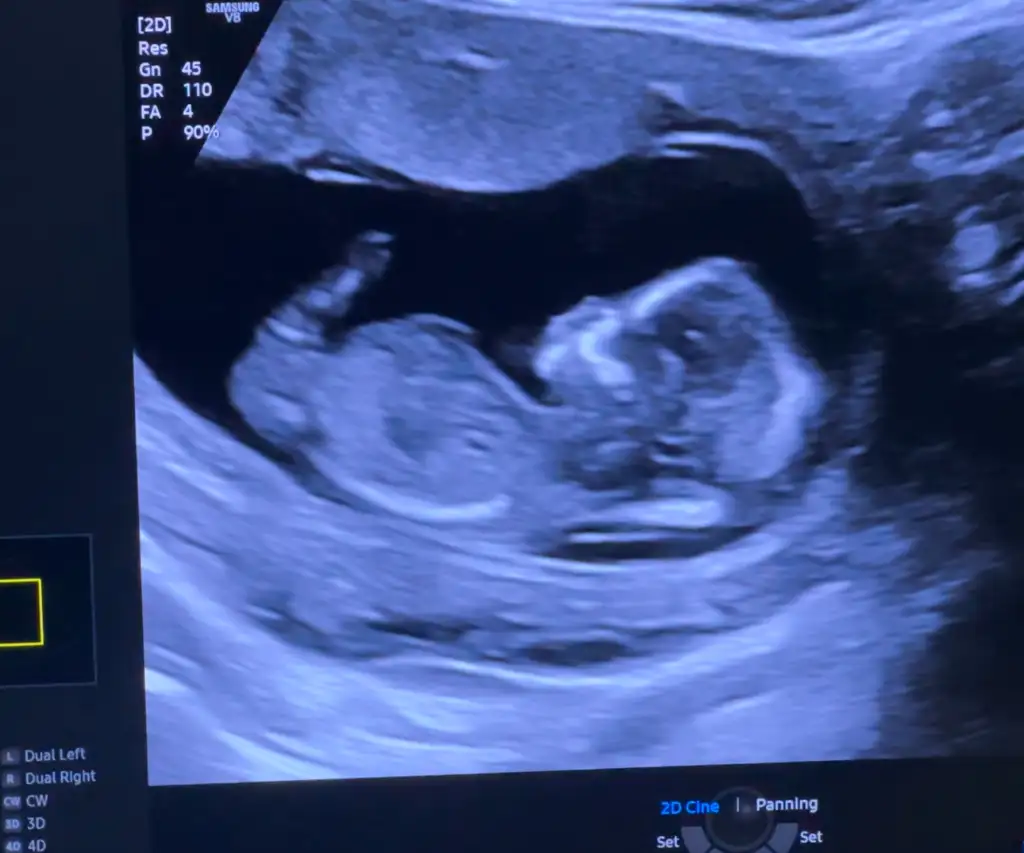

Benim de kusmalarim coktu hastaneye her gün git gel yapip serum takiyorlardi şimdi iste 15 haftaligim.bir de reflü çıkınca çok zorladi.sadece yatıyorum bir oğlum var eşim izin aldı da o bakıyor bize.bir haftadır kusmak yok maşallah diyordum.dun akşam taze fasulye vardi iki belki üç kaşık aldım.saatlerce refluyle sıktı zorladı yatarken de kustum rahatladim diyeyim.bu arada ultrason kagidimi atacağım bulayım bende tahmin istiyorum.daha önce de atmıştım aslında5 kilo verdim 4 gün hastanede yattım anca toparladım kendimi

Sanki kese erkek daha nub vs gözükmüyor ama bir tek keseden bakabiliriz :)Kızlar beni de yorumlar mısınız 17 aralıkta ikili taramaya gidicem inşallah gösterir ama bilemedim

Bana %70 kız dedi ama oğluşum olacak pek doğru söylemiyorBurda nub paralel degil mi chatgpt delirticek buna açılı diyor. Chatgpt yanlış yorunladığı sık mı nub için? Bir de kafası kız bebek mi sizce

oyy boncuk maşallah ellerini ensesine mi atmış annesi yoksa bana mı öyle geldiBurda nub paralel degil mi chatgpt delirticek buna açılı diyor. Chatgpt yanlış yorunladığı sık mı nub için? Bir de kafası kız bebek mi sizce

Aa cidden ellerini ensesine atmıs galiba hahah demeseniz asla fark etmezdim :))oyy boncuk maşallah ellerini ensesine mi atmış annesi yoksa bana mı öyle geldi

Zaten aynı görüntüye farklı yorum yazıyor genelde :dBana %70 kız dedi ama oğluşum olacak pek doğru söylemiyor